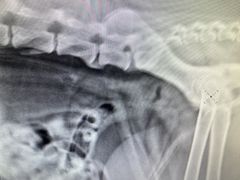

• 小叮当动物医院·骨科·眼科

• -小叮当动物医院·骨科·眼科

Vv | 22-04-09